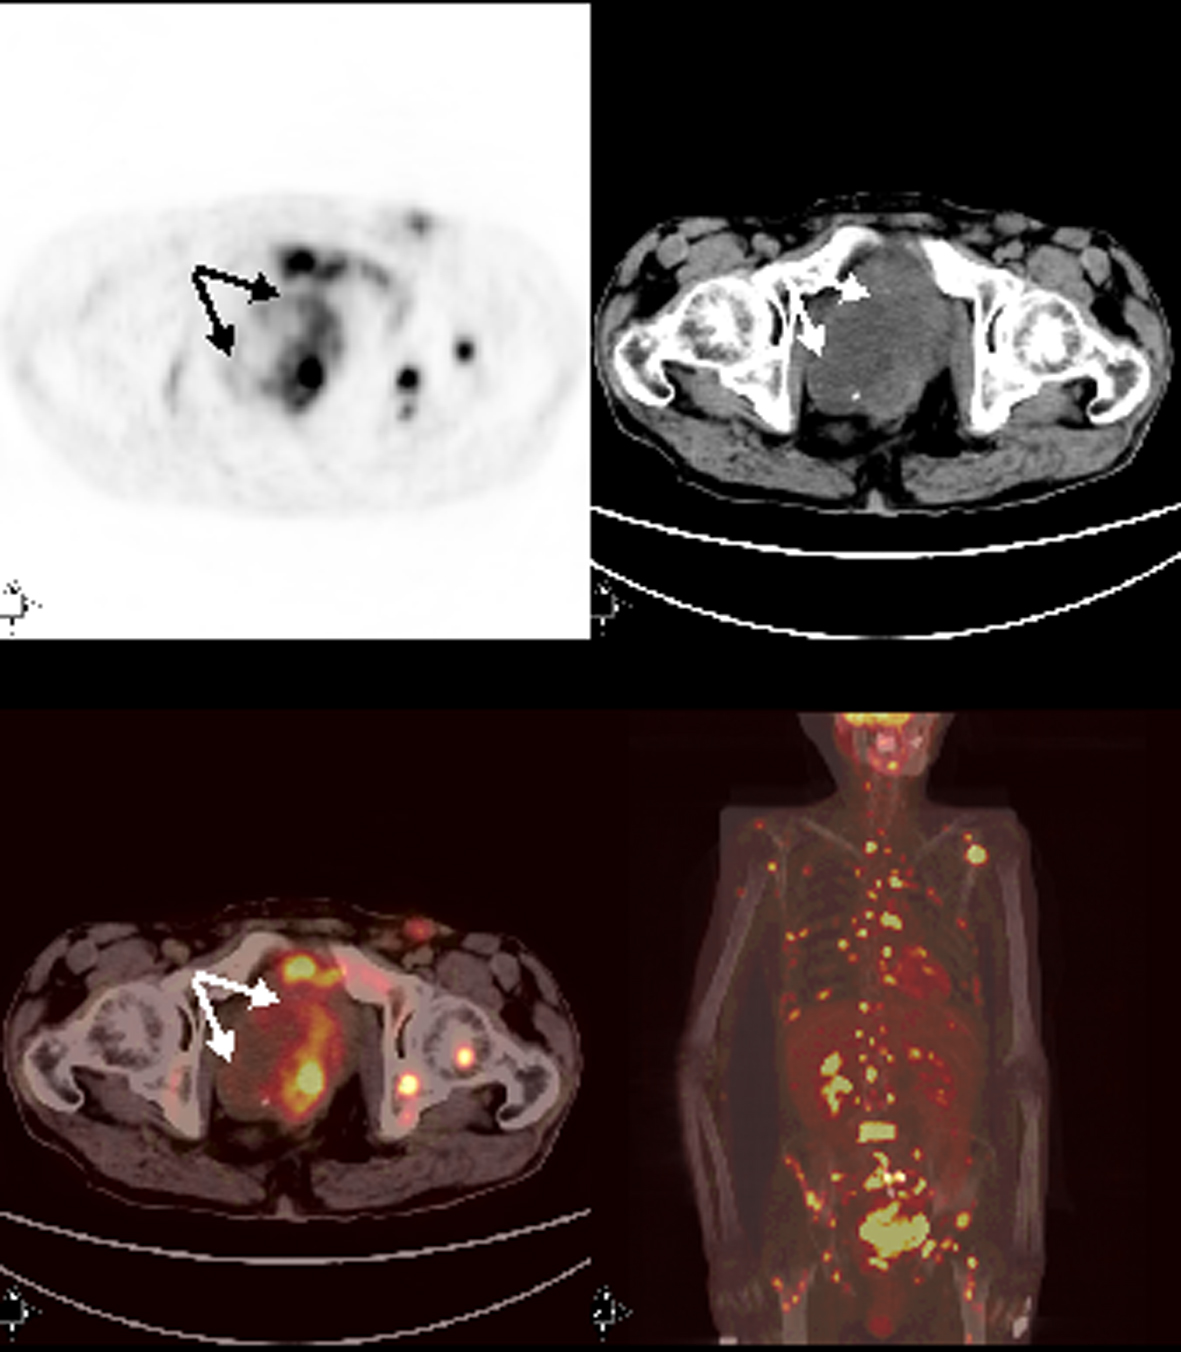

Patient 7

A 56-year-old male patient who was on follow-up for rectosigmoid colon cancer revelaed a pelvic mass on abdominal CT. FDG-PET/CT performed for staging showed hypermetabolic mass consistent with recurrence and metastatic lymphadenopaties at the left inguinal, right external iliac and promontorial region. PET/CT also revealed metastatic lesion in the liver and multipl lesions at the bones as well as in the bone marrow (Fig. 3). Bone marrow biopsy was done with absolutely normal blood count directed by PET/CT findings. Bone marrow metastasis was found consistent with poorly differentiated mucinous adenocarcinoma secondary to colon cancer.

![]() Click for large image | Figure 3. Axial and MIP PET/CT images showed primary tumor with intense FDG accumulation in rectosigmoid. There were also multipl bone-bone marrow metastases and extraskeletal metastases with prominent FDG uptake. |